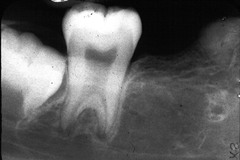

periapical abscess

Front

-Pain, swelling, fistula, slight extrusion of tooth at root -radiographically thickening of PDL and periapical radiolucency ACUTE